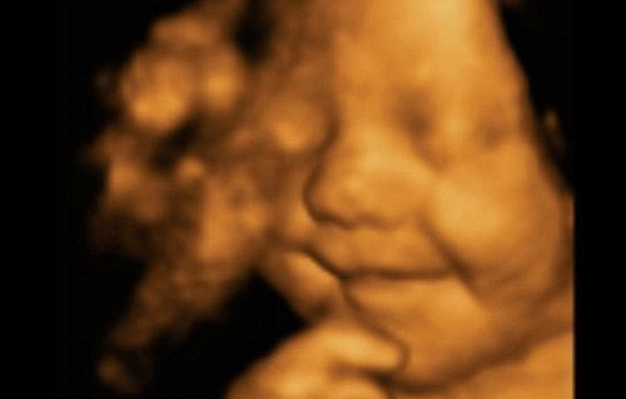

Смята се, че плодът няма съзнание и памет, но още на 24 седмица специалисти са наблюдавали поведение, което свидетелства за истинско (познавателно) мислене. Плодът може да се сърди, да гримасничи, да се усмихва.